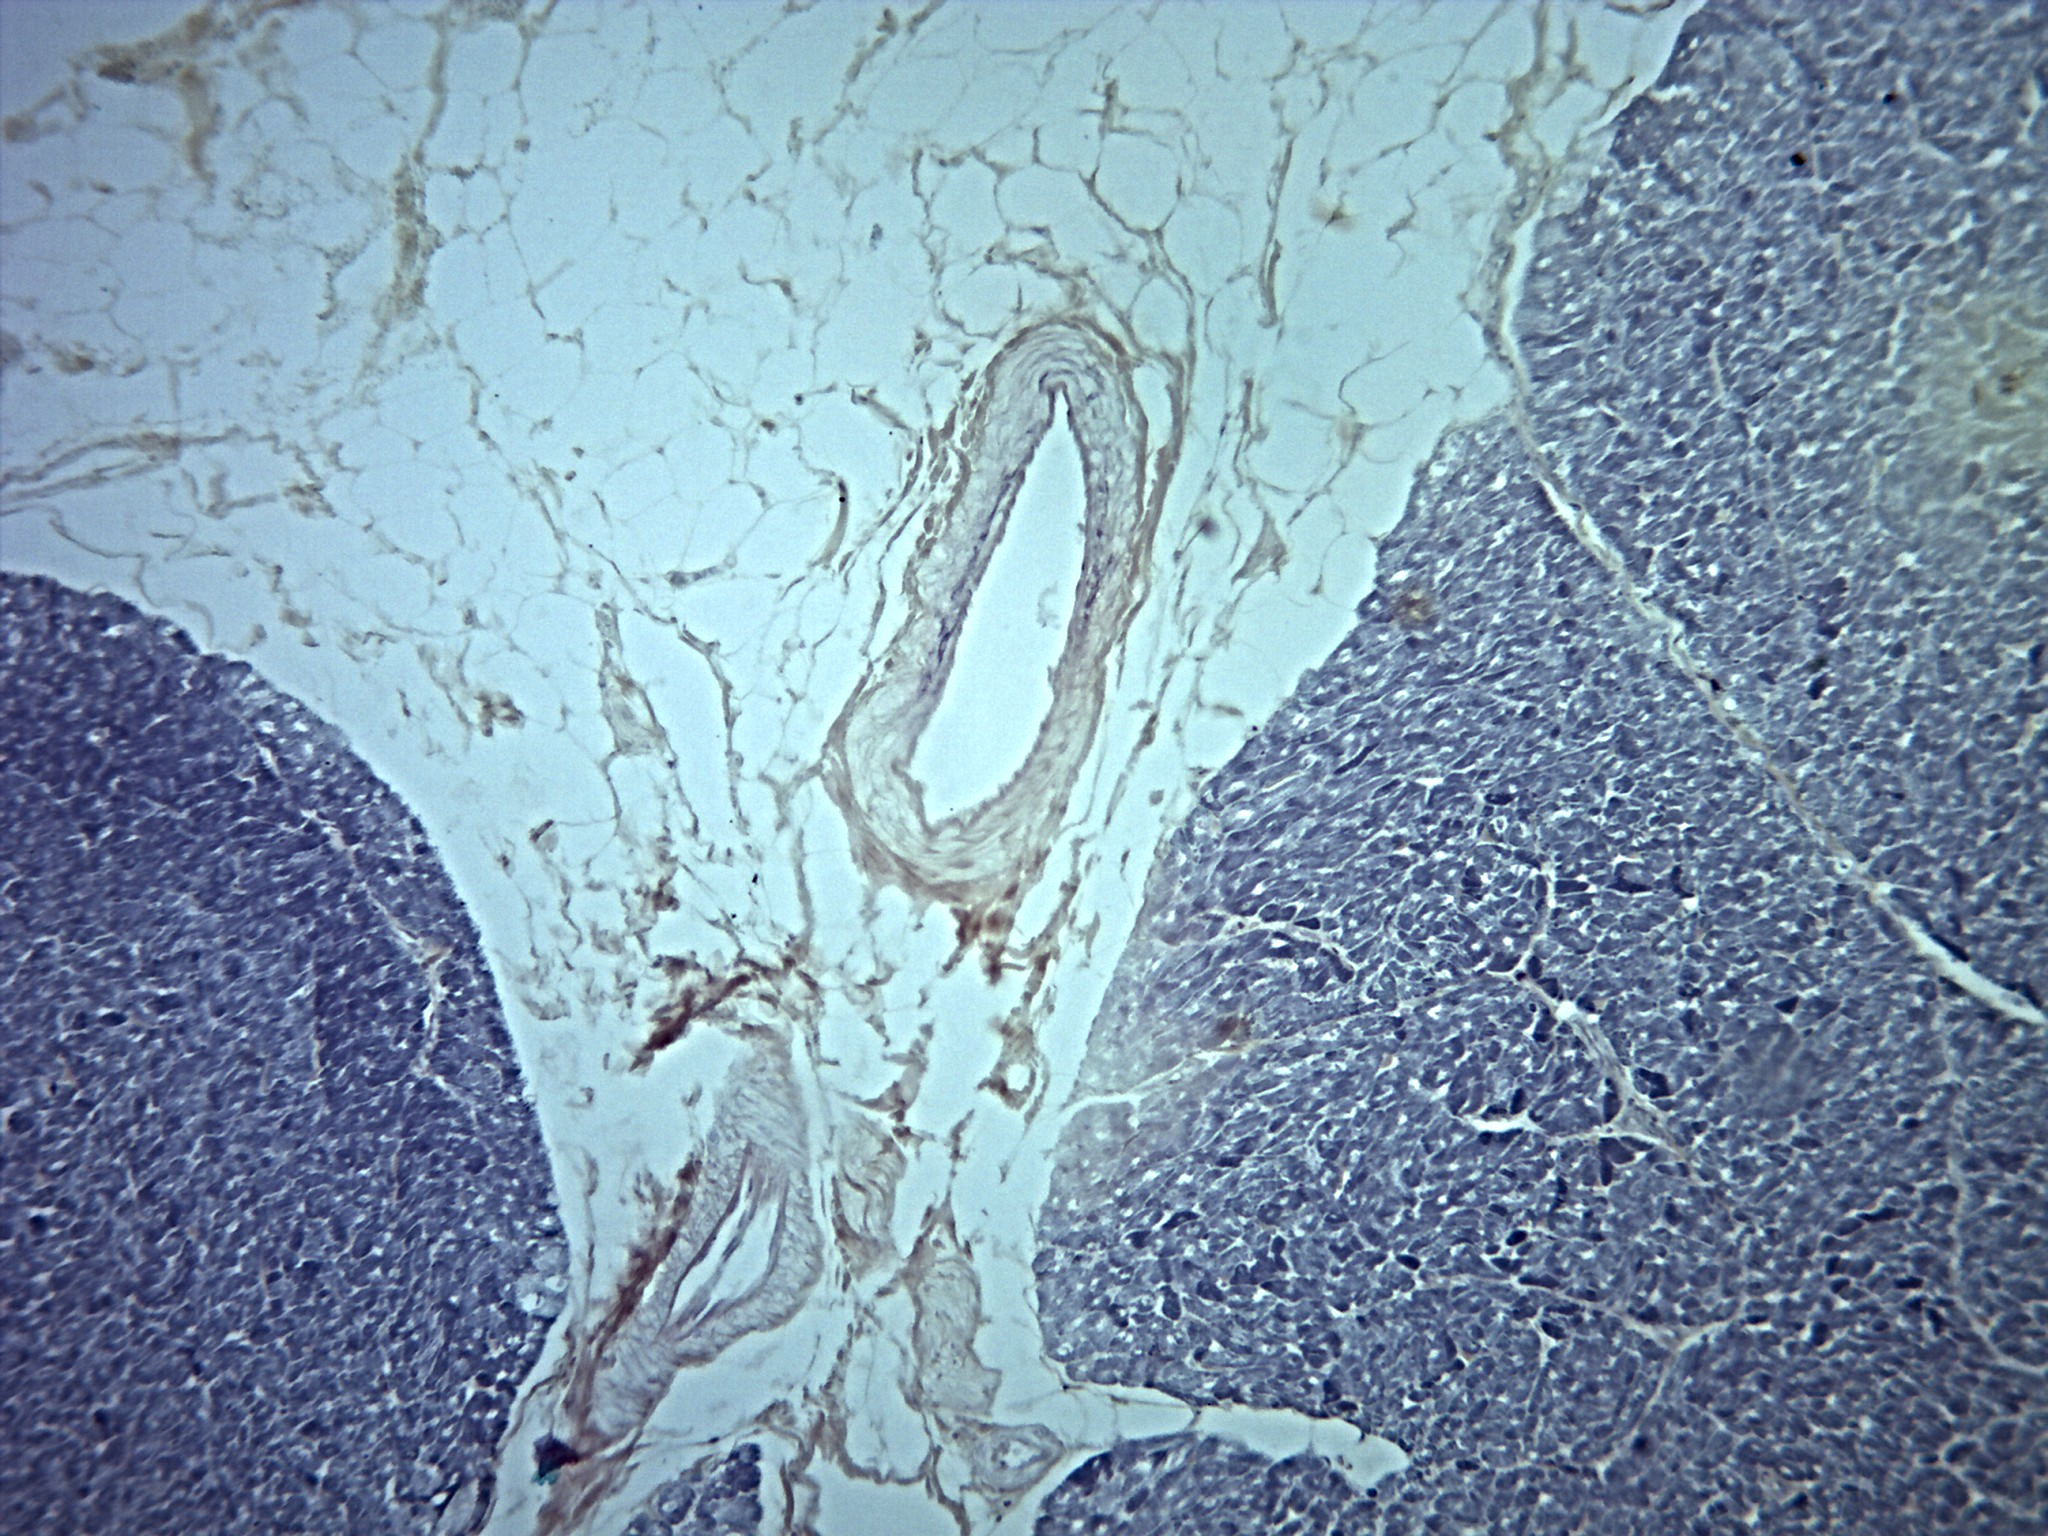

Sistema Circulatório